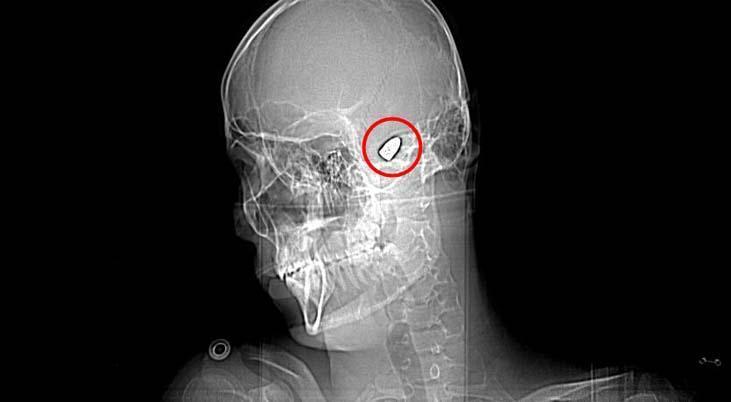

Olay, 5 Kasım 2023’te Bahçelievler Mahallesi 1624’üncü Sokak’ta meydana geldi. Arkadaşları ve ağabeyiyle maça gitmek için konutundan çıkan Yusuf Emre Özbek, birlikte fotoğraf çektirdikten çabucak sonra yere yığıldı. Etraftakilerin hastaneye götürdüğü Yusuf’un çekilen röntgeninde, başında mermi çekirdeği olduğu tespit edildi.

4 gün ağır bakım, 4 gün de serviste tedavi gören Yusuf’un başındaki mermi için tabipler, riskli bölgede olduğu gerekçesiyle müdahale etmedi. Nizamlı olarak denetim edilen Yusuf’ta konuşma zahmeti ve sağ el ve parmaklarında zayıflık belirtileri ortaya çıkınca, fizik tedavi süreci başladı.